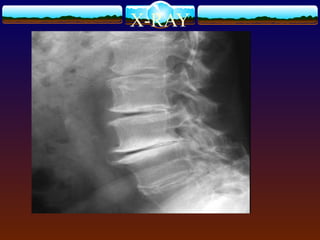

Imaging Studies

 lumbar AP, lateral, and oblique views.

X-RAY